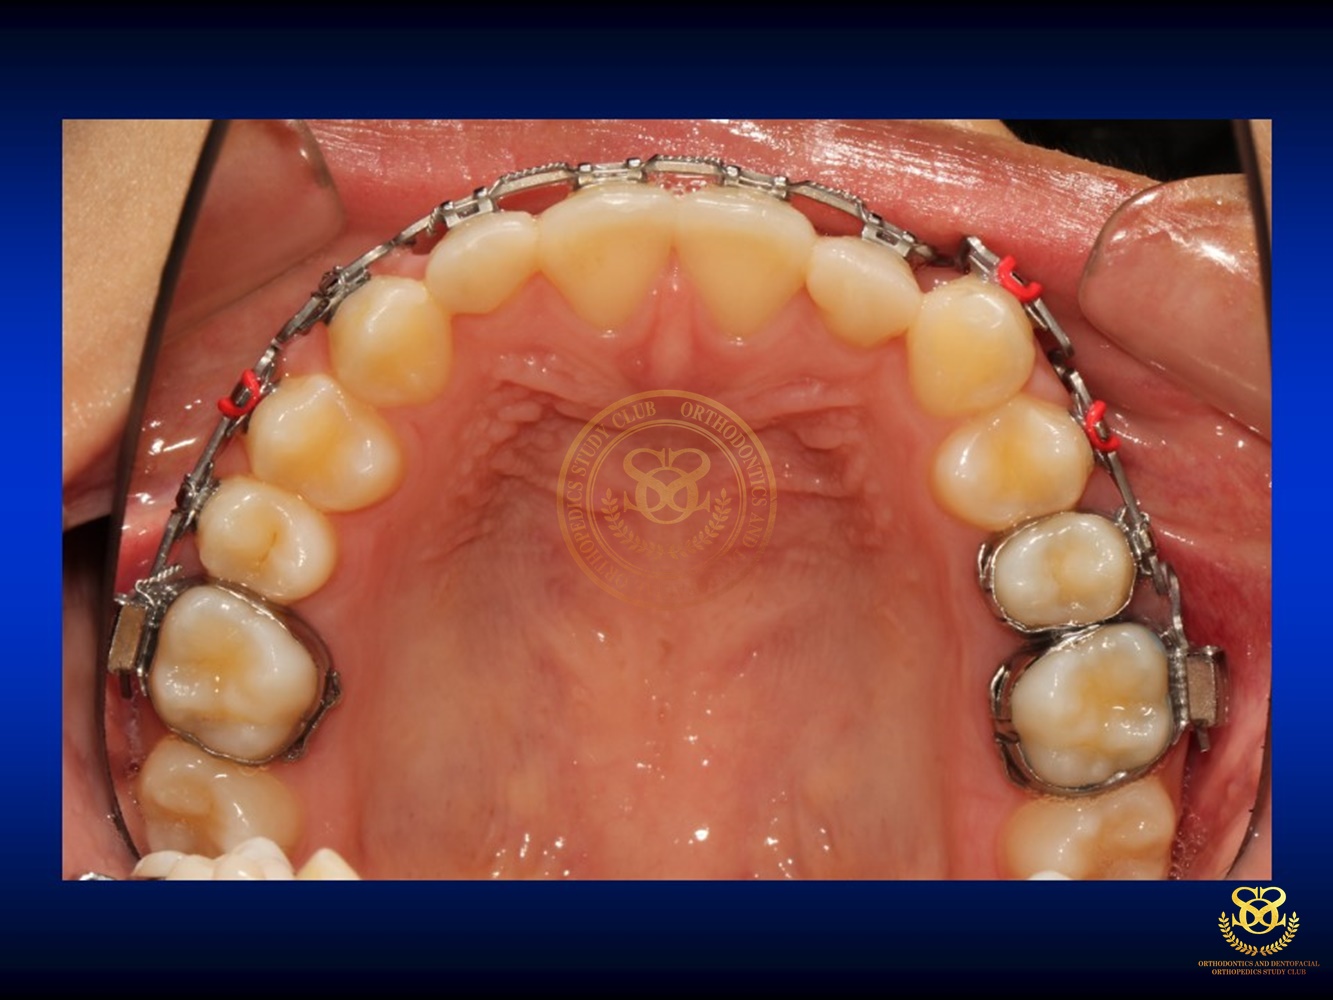

เคสตัวอย่าง Ben.Early Class III Tx.v.2018.CURRENT 2019-10-181168 views0 By Dr.Schwan Somsiri Share Share Share